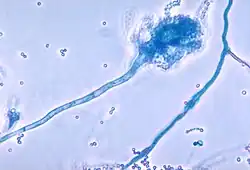

Otros síntomas incluyen expectoración de sangre o esputo sanguinolento, dilatación crónica de los bronquios o bronquiolos (bronquiectasia), elevación de la presión sanguínea en el pulmón, insuficiencia cardíaca, sensación de no estar recibiendo suficiente oxígeno o disnea, insuficiencia respiratoria y atelectasia; podría requerirse soporte ventilatorio.[8] Además de las infecciones bacterianas más comunes, las personas con FQ desarrollan con mayor facilidad otros tipos de enfermedades respiratorias. Entre estas se encuentra la aspergilosis broncopulmonar alérgica, caracterizada por una respuesta de hipersensibilidad ante un hongo (moho) ordinario del género Aspergillus (Aspergillus fumigatus), que agudiza los problemas respiratorios. Otro ejemplo es la infección con el complejo Mycobacterium avium (MAC), grupo de actinobacterias emparentadas con Mycobacterium tuberculosis, que puede ocasionar daños mayores al pulmón, y que no responde a la terapéutica con antibióticos convencionales.

Uno de los modos en que la infección se propaga es por transmisión entre individuos con FQ.[23] En el pasado, era habitual que estos participaran, en forma conjunta, de campamentos veraniegos y otras actividades de esparcimiento.[24][25] Los hospitales alojaban a los pacientes con FQ en un área en común, y el equipamiento de rigor (por ejemplo, los nebulizadores)[26] no era esterilizado entre usos sucesivos.[27] Esto condujo a la transmisión de cepas bacterianas muy peligrosas entre grupos de pacientes. Actualmente, la rutina en establecimientos de atención sanitaria consiste en aislar a estos pacientes unos de otros; además, el personal a cargo de su cuidado, debe vestir batas y guantes para limitar la proliferación de cepas bacterianas virulentas.[28] Con frecuencia, los pacientes afectados por bacterias particularmente peligrosas reciben atención en días y en edificios diferentes a los asignados a quienes no tienen esas infecciones. Además de la infección bacteriana, los pacientes con FQ están predispuestos a la colonización fúngica por la capacidad que tiene algunos hongos de colonizar la vía respiratoria inferior y por los frecuentes ciclos de antibióticos que precisan para el control de la enfermedad.[29] Los hongos que se cultivan con más frecuencia son el Aspergillus fumigatus y la Candida albicans, esta colonización se traduce en una tasa elevada de respuesta inflamatoria frente a los hongos.[30] En la actualidad no está bien definido el papel de los hongos en la FQ, aunque se consideran que son no patógenos, excepto en los casos de aspergilosis invasiva y de aspergilosis broncopulmonar alérgica.